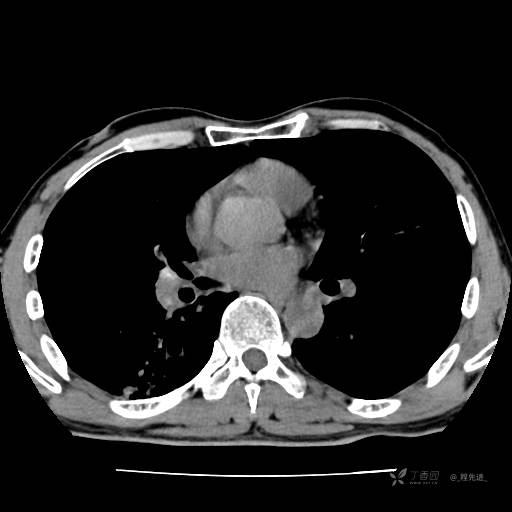

2月特别精彩病例|咳嗽、咳痰20余天,典型病例分享【结果已公布】

患者年龄:51岁

主诉:咳嗽、咳痰20余天

简要病史:20余天前开始出现咳嗽、咳痰症状,阵发性刺激性咳,白色粘痰,不易咳出,无发热,无咯血,无恶心、呕吐等不适,未诊治,咳嗽、咳痰症状持续存在。

体格检查:T:36.3 ℃ P:79 次/分 R:20 次/分 BP:128/64 mmHg,神志清楚,呼吸平稳,双肺呼吸音粗,右下肺闻及细湿性啰音。心率79次/分,节律整齐,各瓣膜听诊区未闻及病理性杂音。腹部未见异常,双下肢无水肿。

辅助检查:我院门诊胸部CT示:如下。心电图:窦性心律;正常心电图。